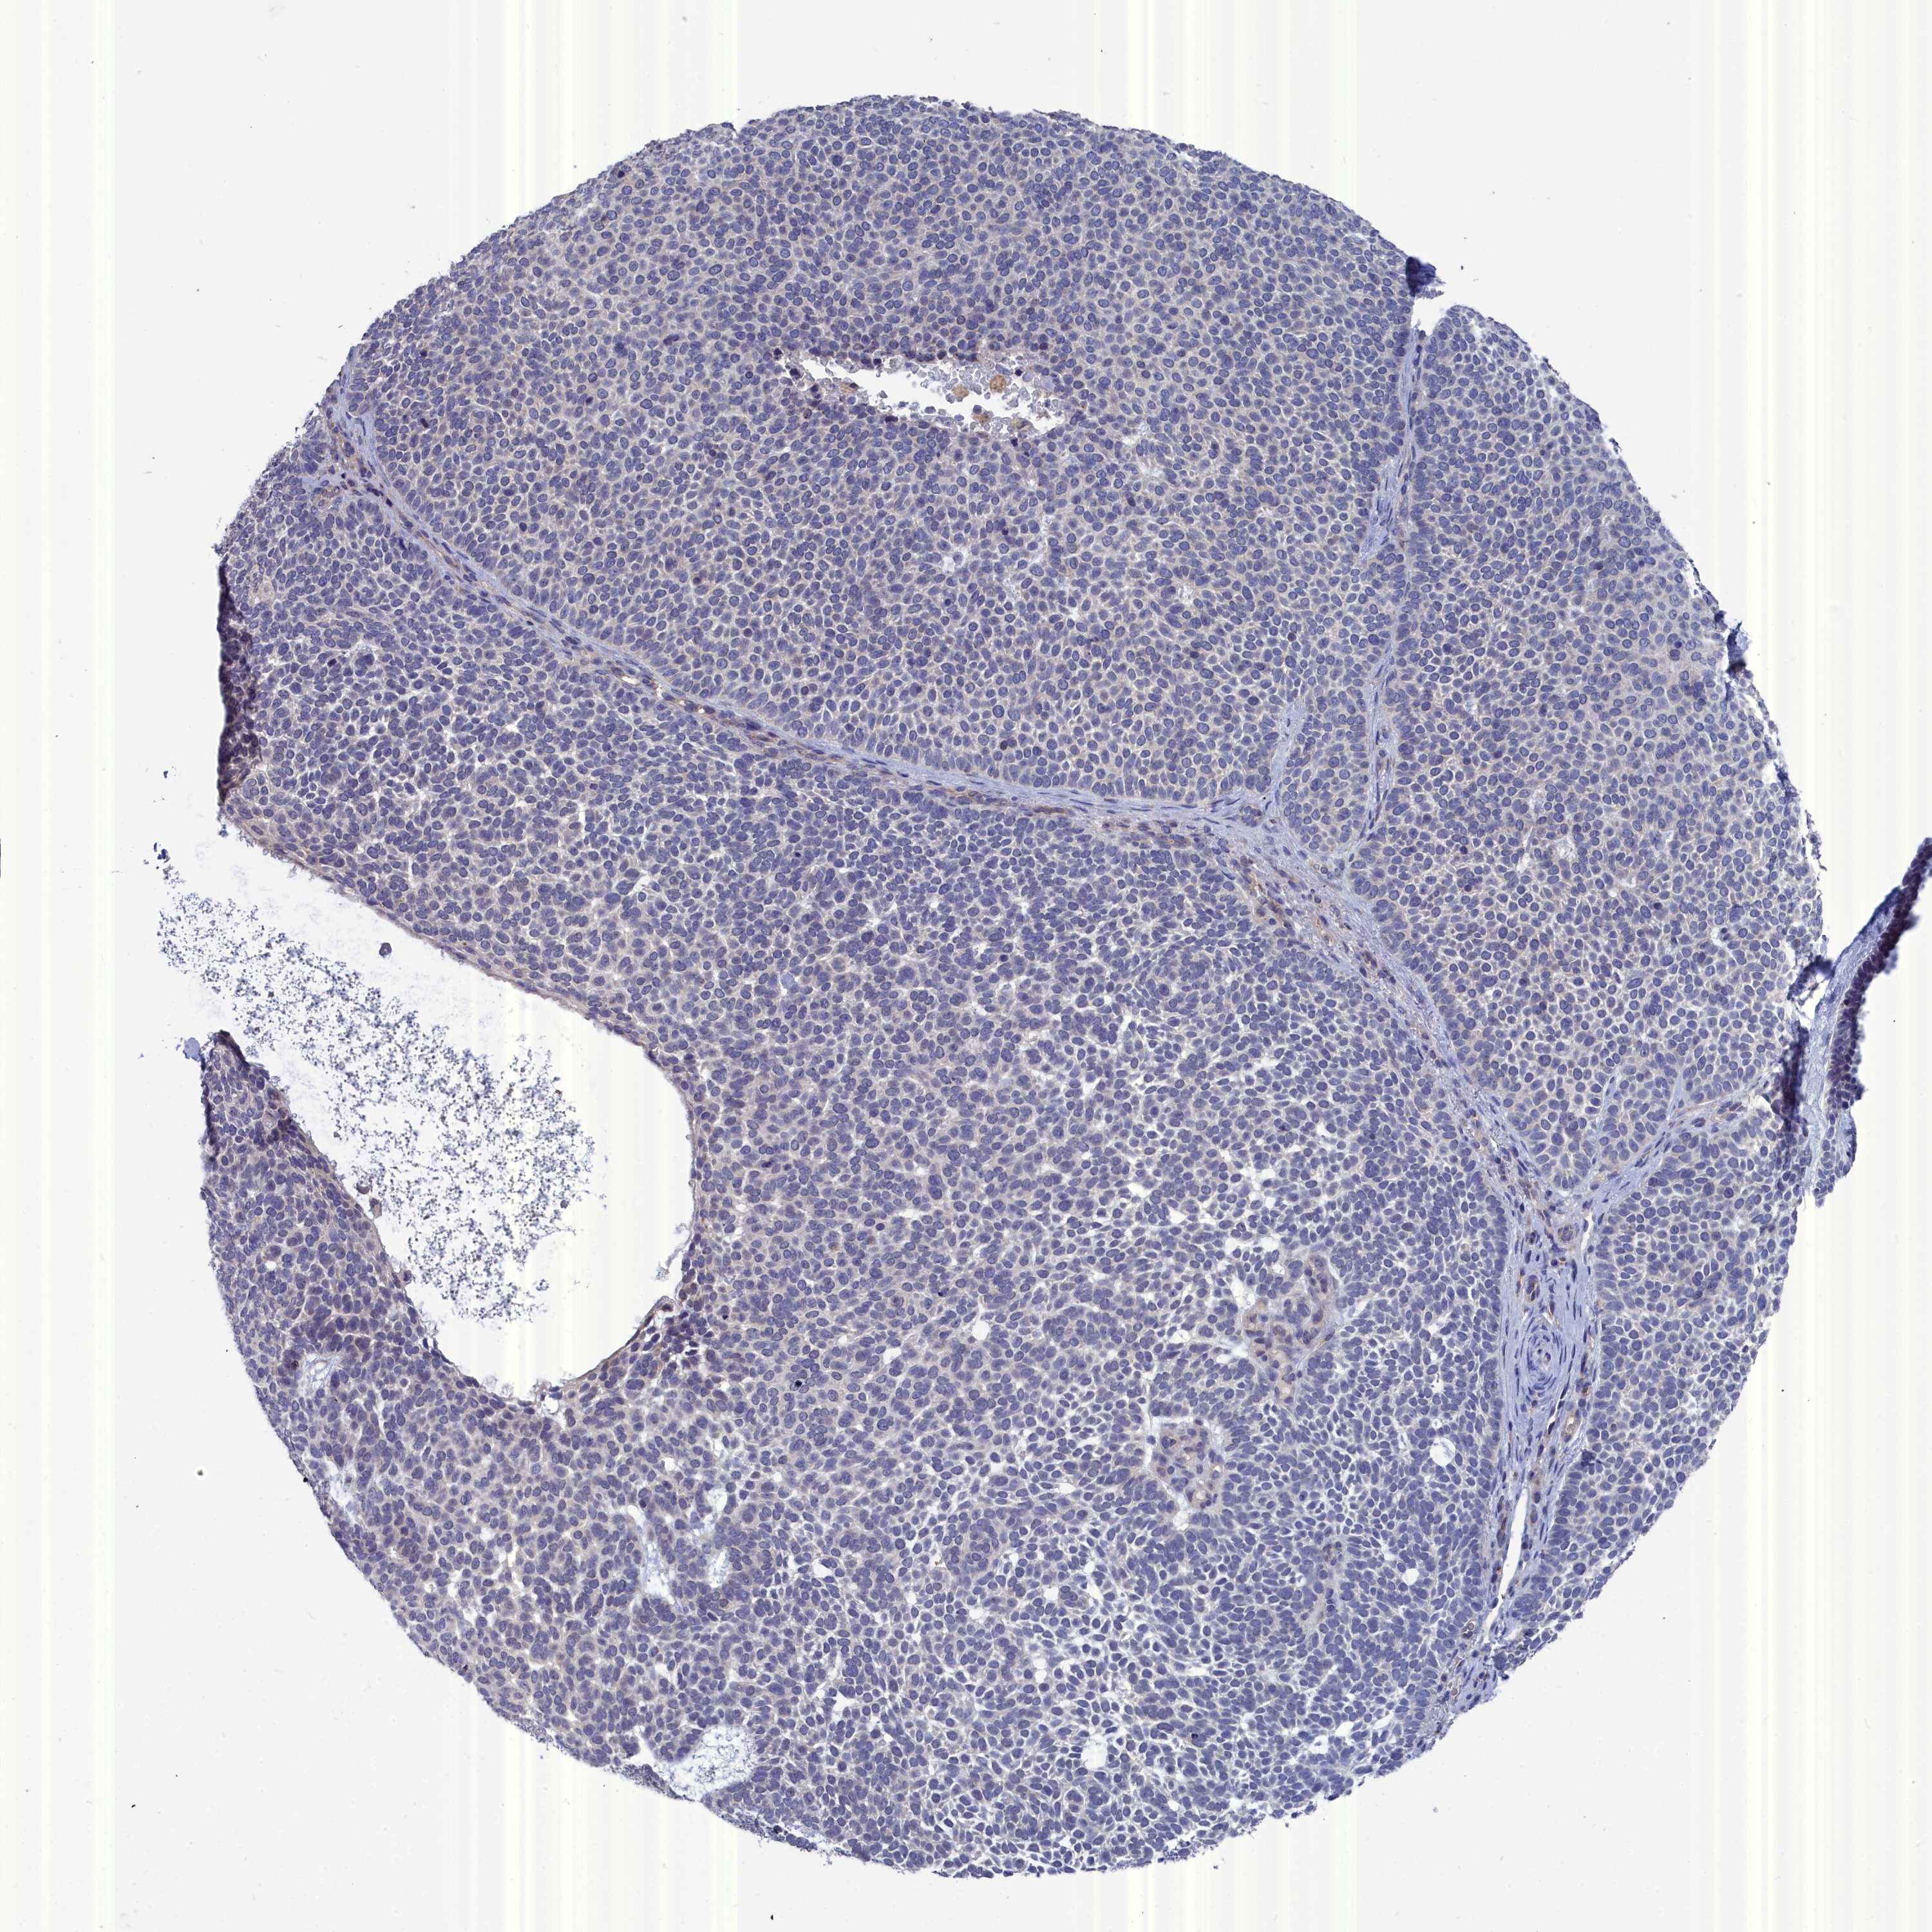

SKIN CANCER - Protein expressioni

A mouse-over function shows sample information and annotation data. Click on an image to view it in a full screen mode. Samples can be filtered based on level of antibody staining by selecting one or several of the following categories: high, medium, low and not detected. The assay and annotation is described here.

Each image is clickable and will lead to virtual microscopy that enables deeper exploration of all samples and also displays staining intensity scores, fraction scores and subcellular localization as well as patient and tissue information for each sample.

Antibody HPA000763

Staining

High

Medium

Low

Not detected

Intensity

Strong

Moderate

Weak

Negative

Quantity

>75%

75%-25%

<25%

None

Location

Nuclear

Cytoplasmic/membranous

Cytoplasmic/membranous,nuclear

Basal cell carcinoma

Squamous cell carcinoma, NOS